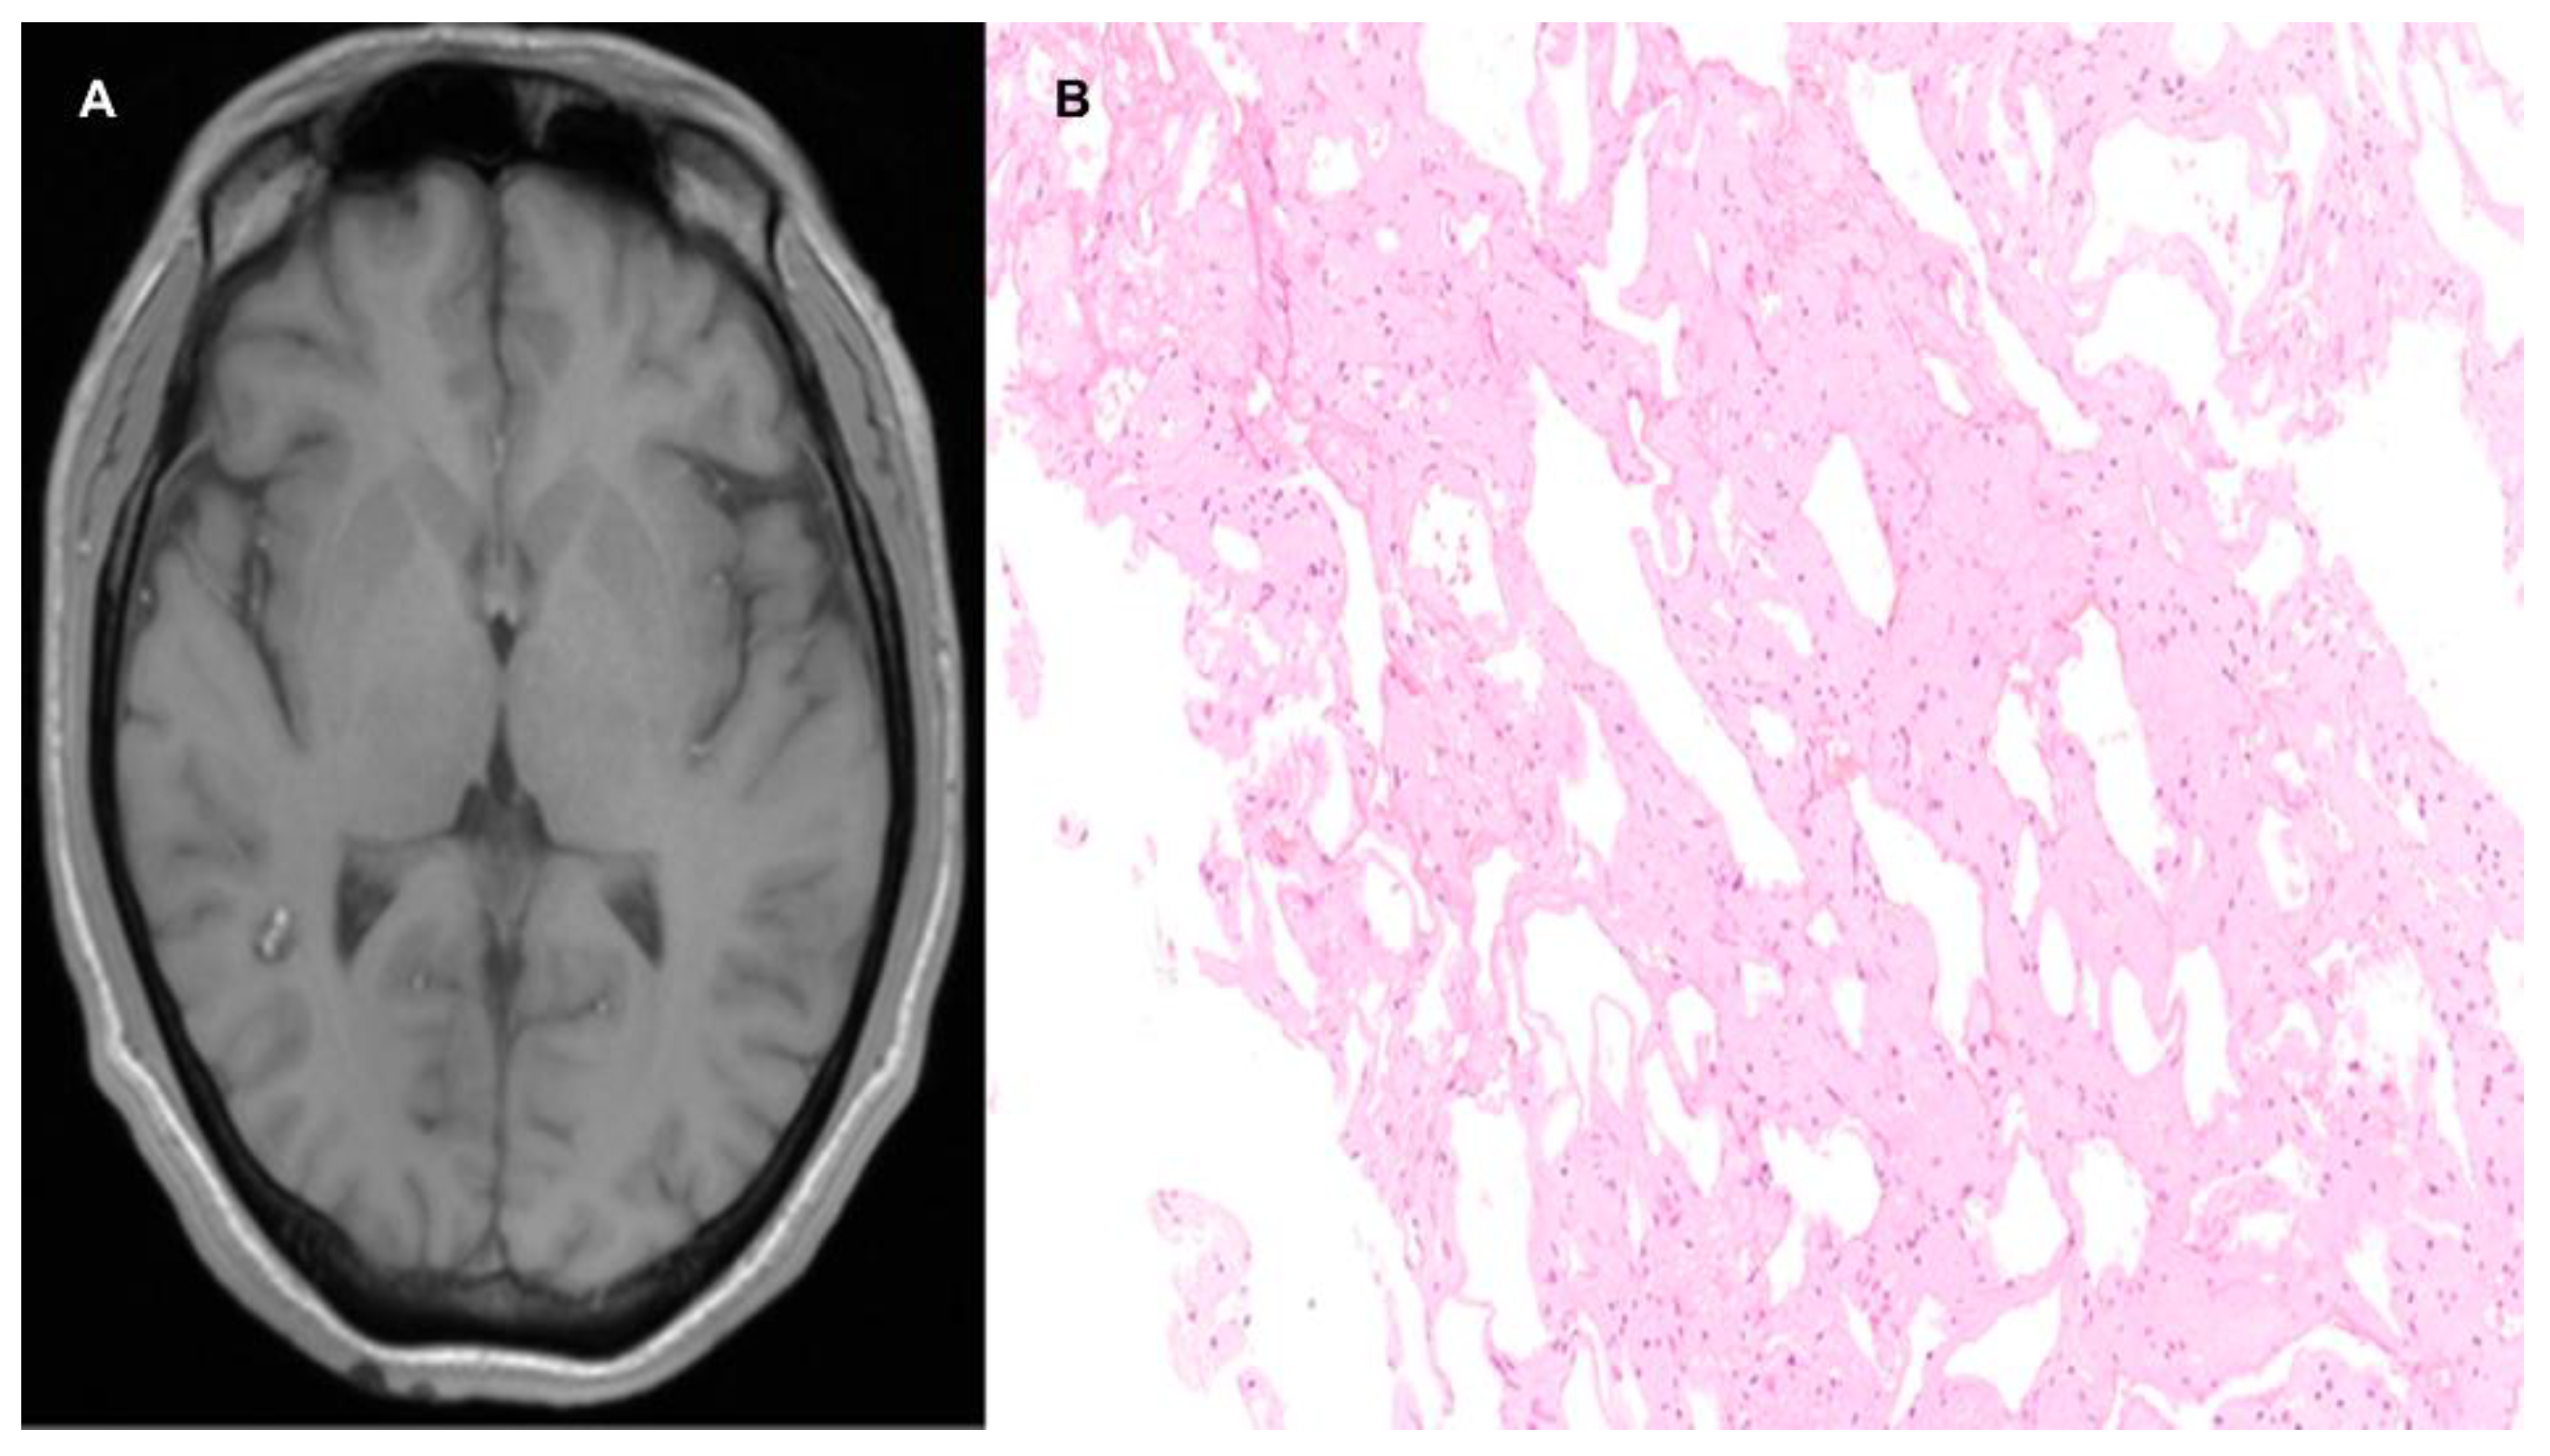

3.3.2. Capillary-Venous Angioma (Sturge–Weber)

- Bertani, R.; Garret, B.; Perret, C.M.; Batista, S.; Koester, S.W.; Azeredo, R.; Guimarães Cavalcante Carlos de Carvalho, T.; Almeida, J.A. Undiagnosed Sturge-Weber Syndrome as a Differential Diagnosis of Seizures and Deep Cerebral Venous System Dilation: A Case Report. Cureus 2021, 13, e19111. [Google Scholar] [CrossRef]